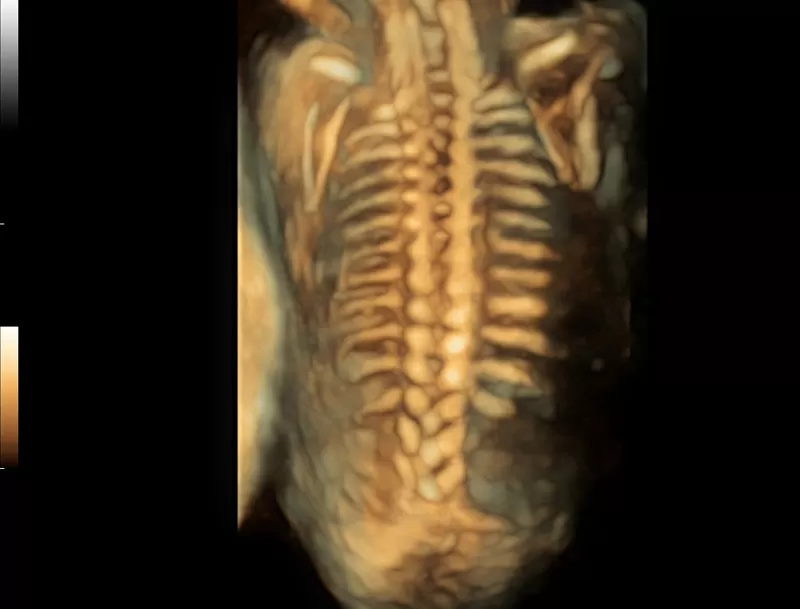

Στη διάθεση σας θα βρίσκονται καταρτισμένοι συνεργάτες μας οι οποίοι θα αναλάβουν να σας παρουσιάσουν τις δυνατότητες του Premium υπερηχογράφου Resona που αποτελεί μια πραγματικά επαναστατική πλατφόρμα, με δεκαπλάσια ταχύτητα σάρωσης χάρις στη μοναδική τεχνολογία zone sonography technology ZST+ που διαθέτει.

Η σειρά Resona ξεχωρίζει όχι μόνο για την κορυφαία απεικονιστική της τεχνολογία αλλά και για τα ευέλικτα εργαλεία ανάλυσης, προσφέροντας ποιότητα απεικόνισης υψηλού επιπέδου και αυξημένη διαγνωστική ακρίβεια.

- Dynamic Focusing